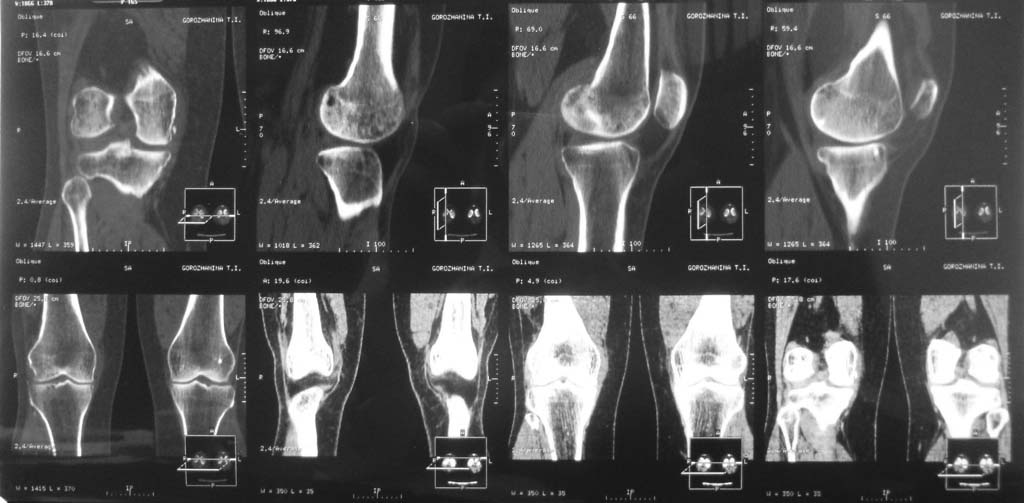

кистовидная перестройка дистального метафиза бера

Пациентка Г. 50 лет

жалобы на боль в коленном суставе в течении 1 года. консультирована краевым ортопедом выставлен DS: Синдром медиопателярной связки коленного сустава. Тактика дальнейшего ведения.

Боль ни с чем не связывает, усиление боли при смене погоды и ночью. Стабильность связочного аппарата сохранена.

Хотелось по подробнее о болях в коленном суставе (постонная, при нагрузках, ночные и тд). Была ли травма? Если травмы не было ... то вероятнее всего первые признаки хондрамаляции. Можно провести курс консервативного лечения, если незначительный эффект -то артроскопия